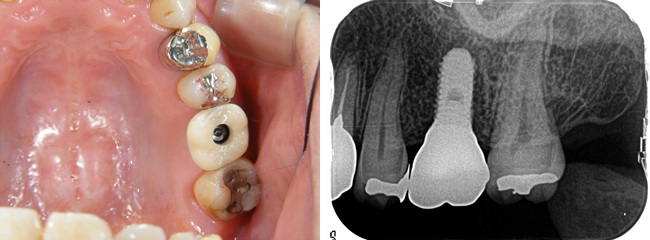

ネジ穴を詰め物でふさいで完成です。

専用の道具で必要に応じて着脱することが可能です。

ネジの緩みや清掃状態などのチェックやアフターメンテナンスを定期的に行います。